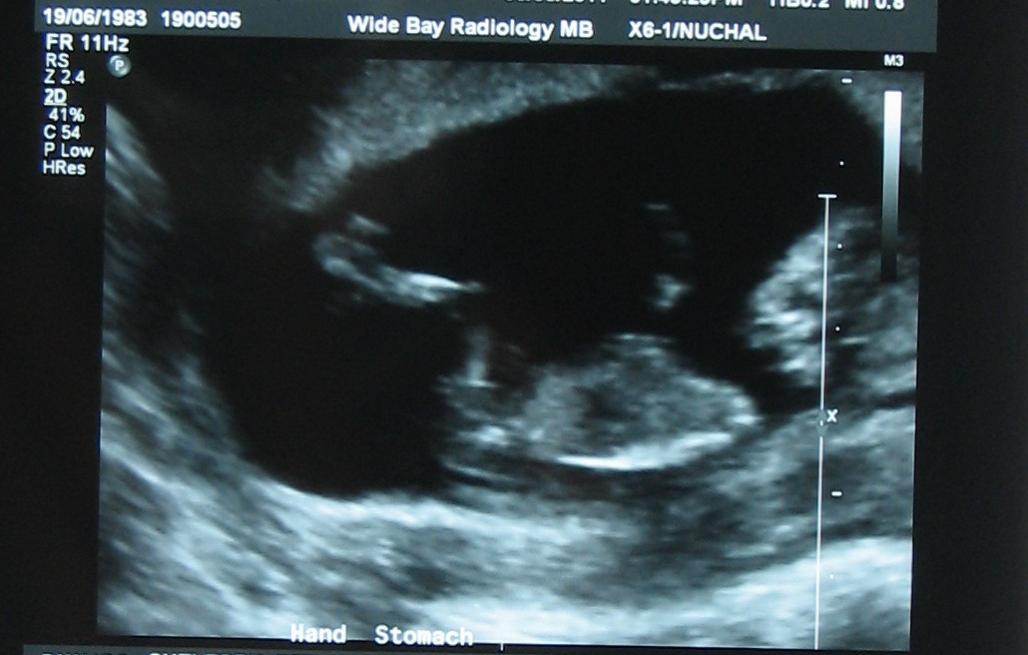

This is from 12 weeks 3 days. Thanks heaps to anyone who take a look & gives a guess.Attachment 594Attachment 593